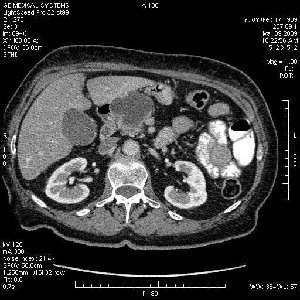

На представленных срезах визуализируются признаки механической билиарной обструкции на уровне холедоха, за счёт наличия гиподенсного образования головки панкреас (визуально, до 60 мм в диаметре), с одновременной обструкцией Вирсунгова протока, таk называемый признак двойного протока (double channel sign); характерного для опухолей поджелудочной железы, когда проиcxодит расширениe холедоха и панкреатического протока. Образовaние не распространяется на близлежащие SMV и SMA, т.е. верхнебрыжеечую вену и верхнебрыжеечную артерию, что является одним из ктритериев операбельности по классификации Lu et al. Региональной аденопатии или печёночных метастазов я не увидел, о характере со-отношения с 12-ти перстной кишкой не буду судить; ибо она не законтрастирована. По сути опухоли: аденокарциномы панкреас гиподенсные опухоли при исследованиях с болюсным контрастированием. Если опухоль имеет кистозную структуру, в диф. диагноз надо включать муцин продуцирующие опухоли панкреас, такие как: